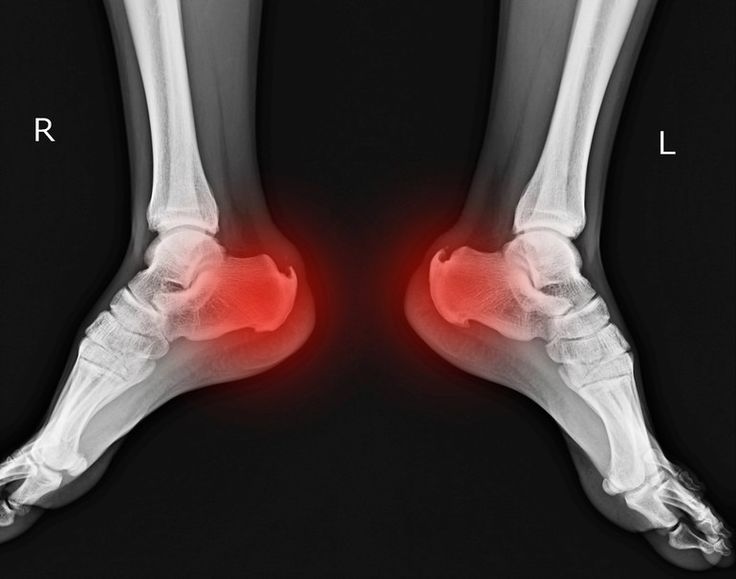

“My ankle arthritis had reached a point where walking even short distances felt impossible. After my joint fusion surgery, the difference is unbelievable. The doctors were supportive, the physiotherapy team guided me throughout recovery, and I can finally walk without limping. Truly life-changing.”

When can I walk after ankle or foot fusion surgery?

You may need to avoid weight-bearing for a few weeks. Your surgeon will guide you based on your healing progress.